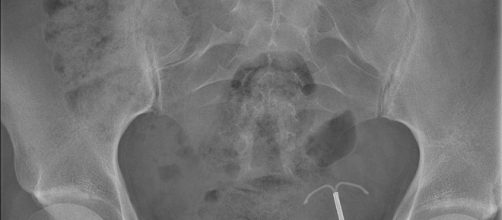

Results of the CT scan and X-ray

Speaking to CNN, Dr. Takeshi Kondo, lead author of the report, concluded that the sponges might have been left during a cesarean section. In the official report, Kondo states that the patient had had two cesarean sections in the same hospital, the last operation being six years ago. The unidentified woman did not have other pelvic or abdominal operations after her last cesarean section. After learning she had been carrying two sponges inside her for six years, the woman went to confront the surgeon responsible, but the doctor refused to admit his mistakes.